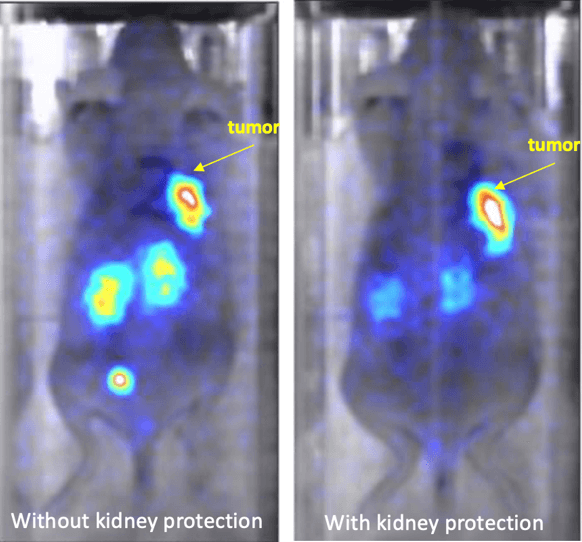

SPECT imaging of IN-111-Dotatate in mice with tumors. Image on the right includes protection of the kidneys, as seen by the reduced signal in this organ. Image Credit: Scintica Instrumentation Inc.

SPECT imaging of IN-111-Dotatate in mice with tumors. Image on the right includes protection of the kidneys, as seen by the reduced signal in this organ. Image Credit: Scintica Instrumentation Inc.